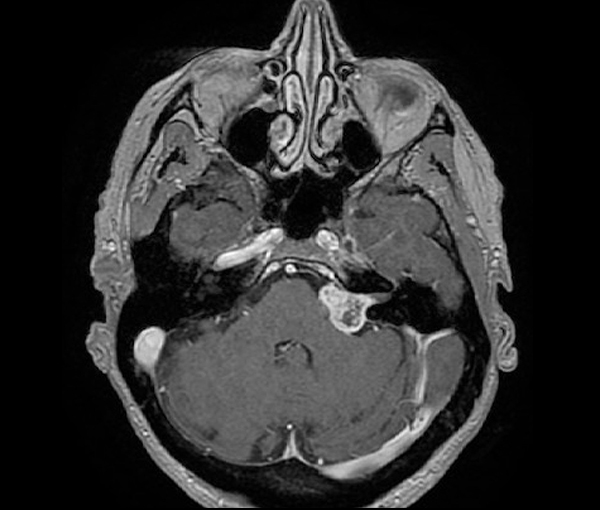

Le scanner montre un hématome sousdural frontopariétal droit subaigu (flèches rouges) Sur un scanner non injecté, le sang frais est hyperdense alors que celui plus ancien est hypodense Mais pendant un certain laps de temps le sang est d'aspect isodense comme le parenchyme cérébral, et c'est le cas sur cette image. Scanners montrant la cartographie fonctionnelle du cerveau pour trois types d’activité mentale (émotion, récompense, exécution d’une tâche) sur deux jours différents. Scanner translation in French English Reverso dictionary, see also 'scander',savonner',scandale',scansion', examples, definition, conjugation.